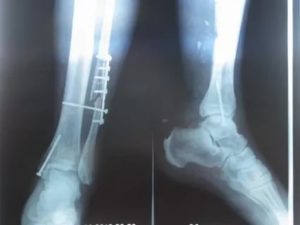

Наиболее часто врачи назначают рентгенологическое обследование и производство снимков. Методика позволяет диагностировать перелом большой и малой берцовой кости. При повреждении нерва показана электронейромиограия.

Рассчитаны фиксаторы на пожизненное использование, но примерно через год после постановки при условии консолидации перелома могут быть удалены. При открытом переломе врач может установить внешней фиксатор или аппарат по методике Илизарова.

Если вытяжение не приносит должного результата, то больному назначается оперативное вмешательство, во время которого костные отломки фиксируются с помощью стержней, шурупов, пластин или аппарата Илизарова.

Пластина